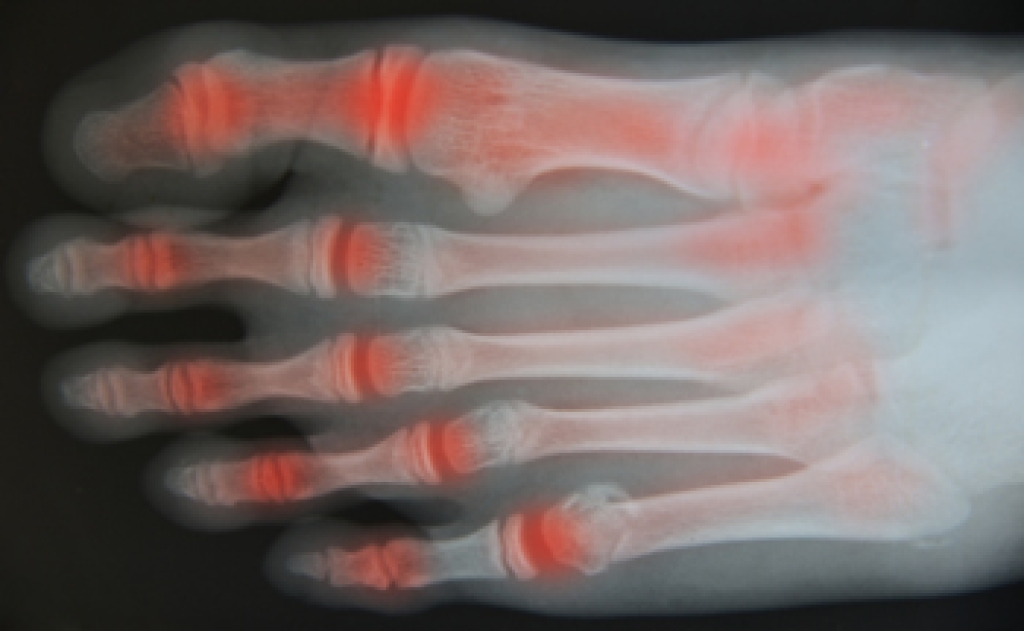

Gout is a form of arthritis that is characterized by sudden, severe attacks of pain, redness, and tenderness in the joints. The condition usually affects the joint at the base of the big toe. A gout attack can occur at any random time, such as the middle of the night while you are asleep.

- Inflammation and Redness -Affected joints may become swollen, tender, warm and red